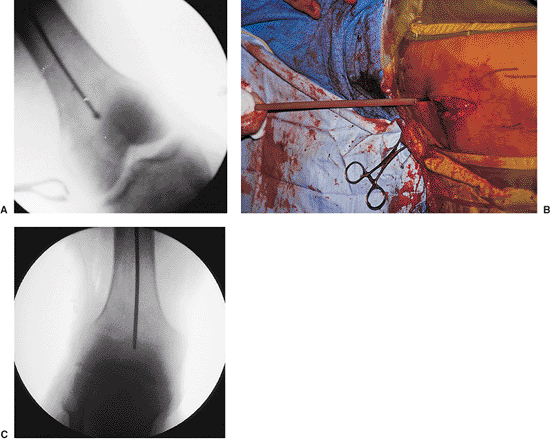

Figures 21.26. A,B.

Fracture reduction with crutch. A combination of maneuvers can be used to reduce the fracture in the sagittal plane. A crutch is often needed to support the distal fragment, which is pulled toward the floor by the two heads of the gastrocnemius muscle. The proximal fragment is pulled anteriorly by the hip flexors. Manual pressure applied on the anterior thigh may assist with reduction. Radiographic conformation of the crutch helps ensure fracture reduction and allows passage of the bead-tipped guide wire. |